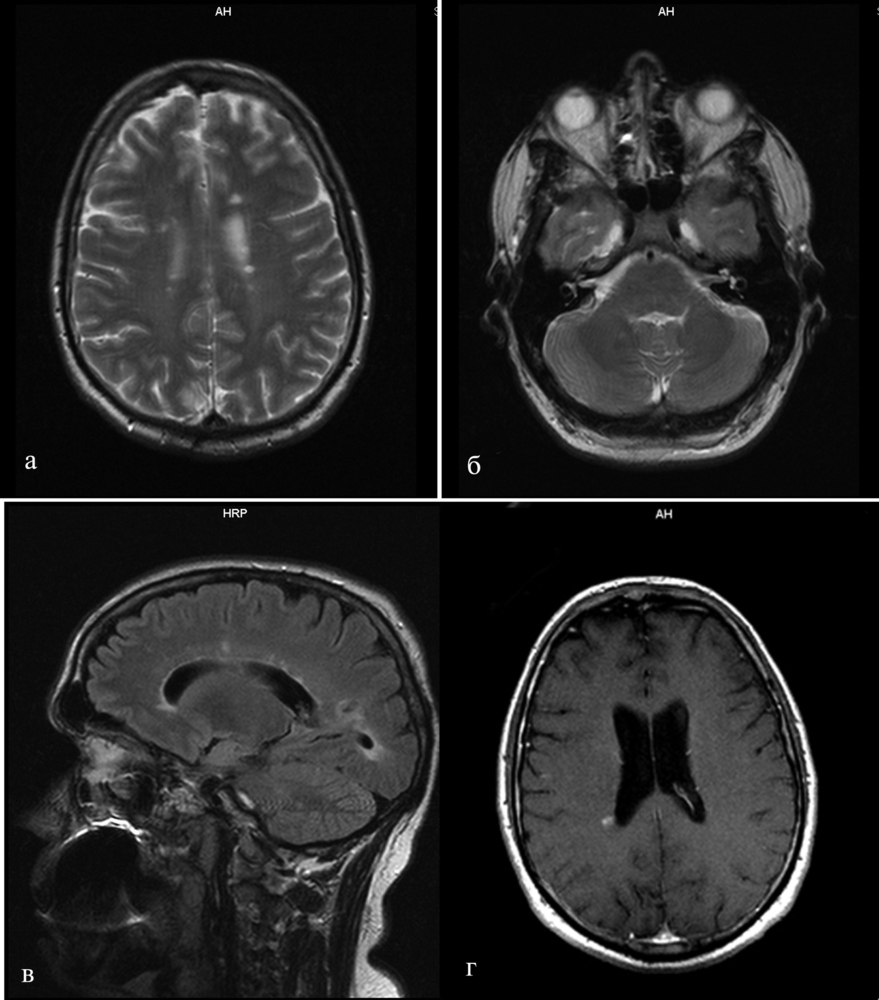

Лабораторные анализы крови и мочи были в норме. По результатам магнитно-резонансной томографии (МРТ) головного и спинного мозга были выявлены множественные очаги демиелинизации величиной 3-7 мм, гиперинтенсивные на Т2-взвешенных изображениях (Т2-ВИ) и гипоинтенсивные на Т1-взвешенных изображениях (Т1-ВИ), локализующиеся в белом веществе больших полушарий мозга, перивентрикулярных и подкорковых отделах, мозолистом теле. Аналогичный единичный очаг наблюдался в правом полушарии мозжечка (рис. 1).

На уровне сегмента С2 определялись 2 интрамедуллярных очага без четких контуров, слабогиперинтенсивные на Т2-ВИ и изоинтенсивные на Т1-ВИ, размерами 4×6 и 4×7 мм. Не исключалось наличие аналогичного очага на уровне сегментов С4-С5 и С5-С6 шейного отдела спинного мозга (рис. 2).

Для верификации диссеминации патологического процесса во времени и установления достоверного диагноза РС пациенту было проведено повторное МРТ-исследование головного мозга через 3 мес. По сравнению с предшествующими результатами МРТ отмечалось появление новых очагов демиелинизации слева в перивентрикулярном отделе и у заднего рога правого бокового желудочка; при введении контраста последний очаг накапливал контрастное вещество (омнискан) (см. рис. 1). Согласно критериям Макдональда [13], пациенту был выставлен диагноз: РС, ремиттирующее течение. Через 3 мес гиперкинезов в руке выявлено не было.